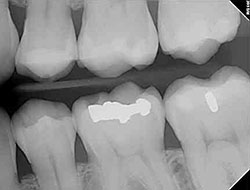

Digital X-Rays

Using the most advanced dental

technology possible is just as important as staying up-to-date on the latest

treatment techniques. Because our practice is dedicated to providing you

with the safest and most convenient treatment options available we utilize

advanced digital X-ray technology in our office.

Digital X-rays provide several advanced imaging options that are designed to save time, provide clearer dental photos and expose patients to less radiation than with traditional X-ray technology.

Our practice is focused on making your dental experience as comfortable as possible. At your next appointment, we’ll be happy to answer any questions you may have.